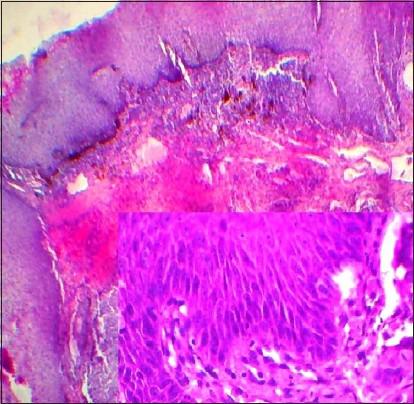

Basaloid squamous cell carcinoma (BSCC) is a distinct variant of conventional squamous cell carcinoma (SCC), predominantly localized in the upper aerodigestive tract. In the head and neck region, the tumor has a strong predilection for extra-laryngeal sites, such as the base of the tongue, tonsil, hypopharynx and supraglottic larynx. BSCC has well-defined histological features, characterized by nesting, lobular and trabecular arrangement of basaloid cells. Central comedonecrosis within the cell nests, cells with nuclear palisading and high-grade dysplasia in overlying mucosa are the main characteristics. The tumor is considered to be highly aggressive and often presents itself as an advanced stage lesion, thus demanding early diagnosis and prompt treatment. We here report a case of 72-year-old male diagnosed with BSCC involving the right tonsillar region.

基底样鳞状细胞癌(BSCC)是传统鳞状细胞癌(SCC)的一种独特变体,主要位于上消化道。在头颈部区域,该肿瘤强烈倾向于喉外部位,如舌根、扁桃体、下咽和声门上喉。BSCC具有明确的组织学特征,其特点是基底样细胞呈巢状、小叶状和小梁状排列。细胞巢内的中央粉刺样坏死、细胞核呈栅栏状排列的细胞以及覆盖黏膜的高级别发育异常是主要特征。该肿瘤被认为具有高度侵袭性,常表现为晚期病变,因此需要早期诊断和及时治疗。我们在此报告一例72岁男性被诊断为累及右侧扁桃体区域的基底样鳞状细胞癌。